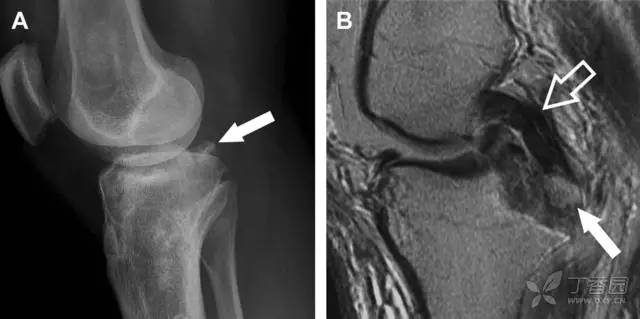

图 2 扭伤后的股骨外侧髁凹陷征

A 侧位片示股骨外侧髁凹陷。B MRI 矢状位 T2 加权像示股骨外侧髁及胫骨后外侧骨挫伤(空箭头)。胫骨近端随着后交叉韧带撕裂发生移位,露出外侧半月板的后角(弧形箭头)。

胫骨后外侧小片骨皮质的压缩性骨折,可能是旋转移位损伤的唯一证据(图 3)。这种骨折在常规膝关节平片很难发现,若怀疑存在骨折,行下肢内旋斜位片检查可诊断。

图 3 胫骨后外侧碎片骨折

A 正位片示胫骨后外侧处可见一压缩骨折的小碎片(方框)。这是胫骨撞击股骨外侧髁旋转移位时所致。B 另一位患者的 MRI 矢状位 T1 加权像示胫骨后外侧骨折碎片(箭头)。